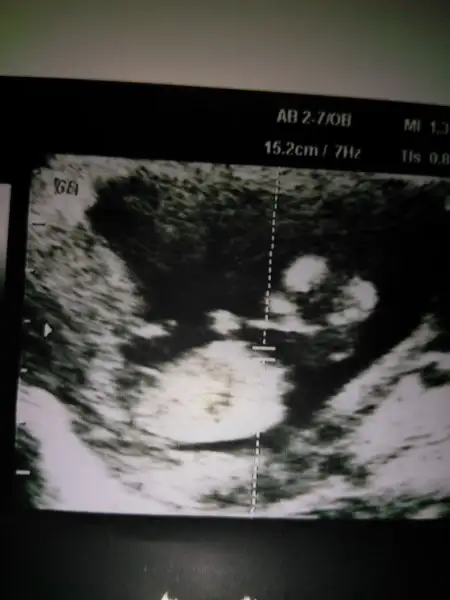

Bize de bakabilir misiniz 7 haftalik

Eki Görüntüle 1716946

Kız gibi cnm.